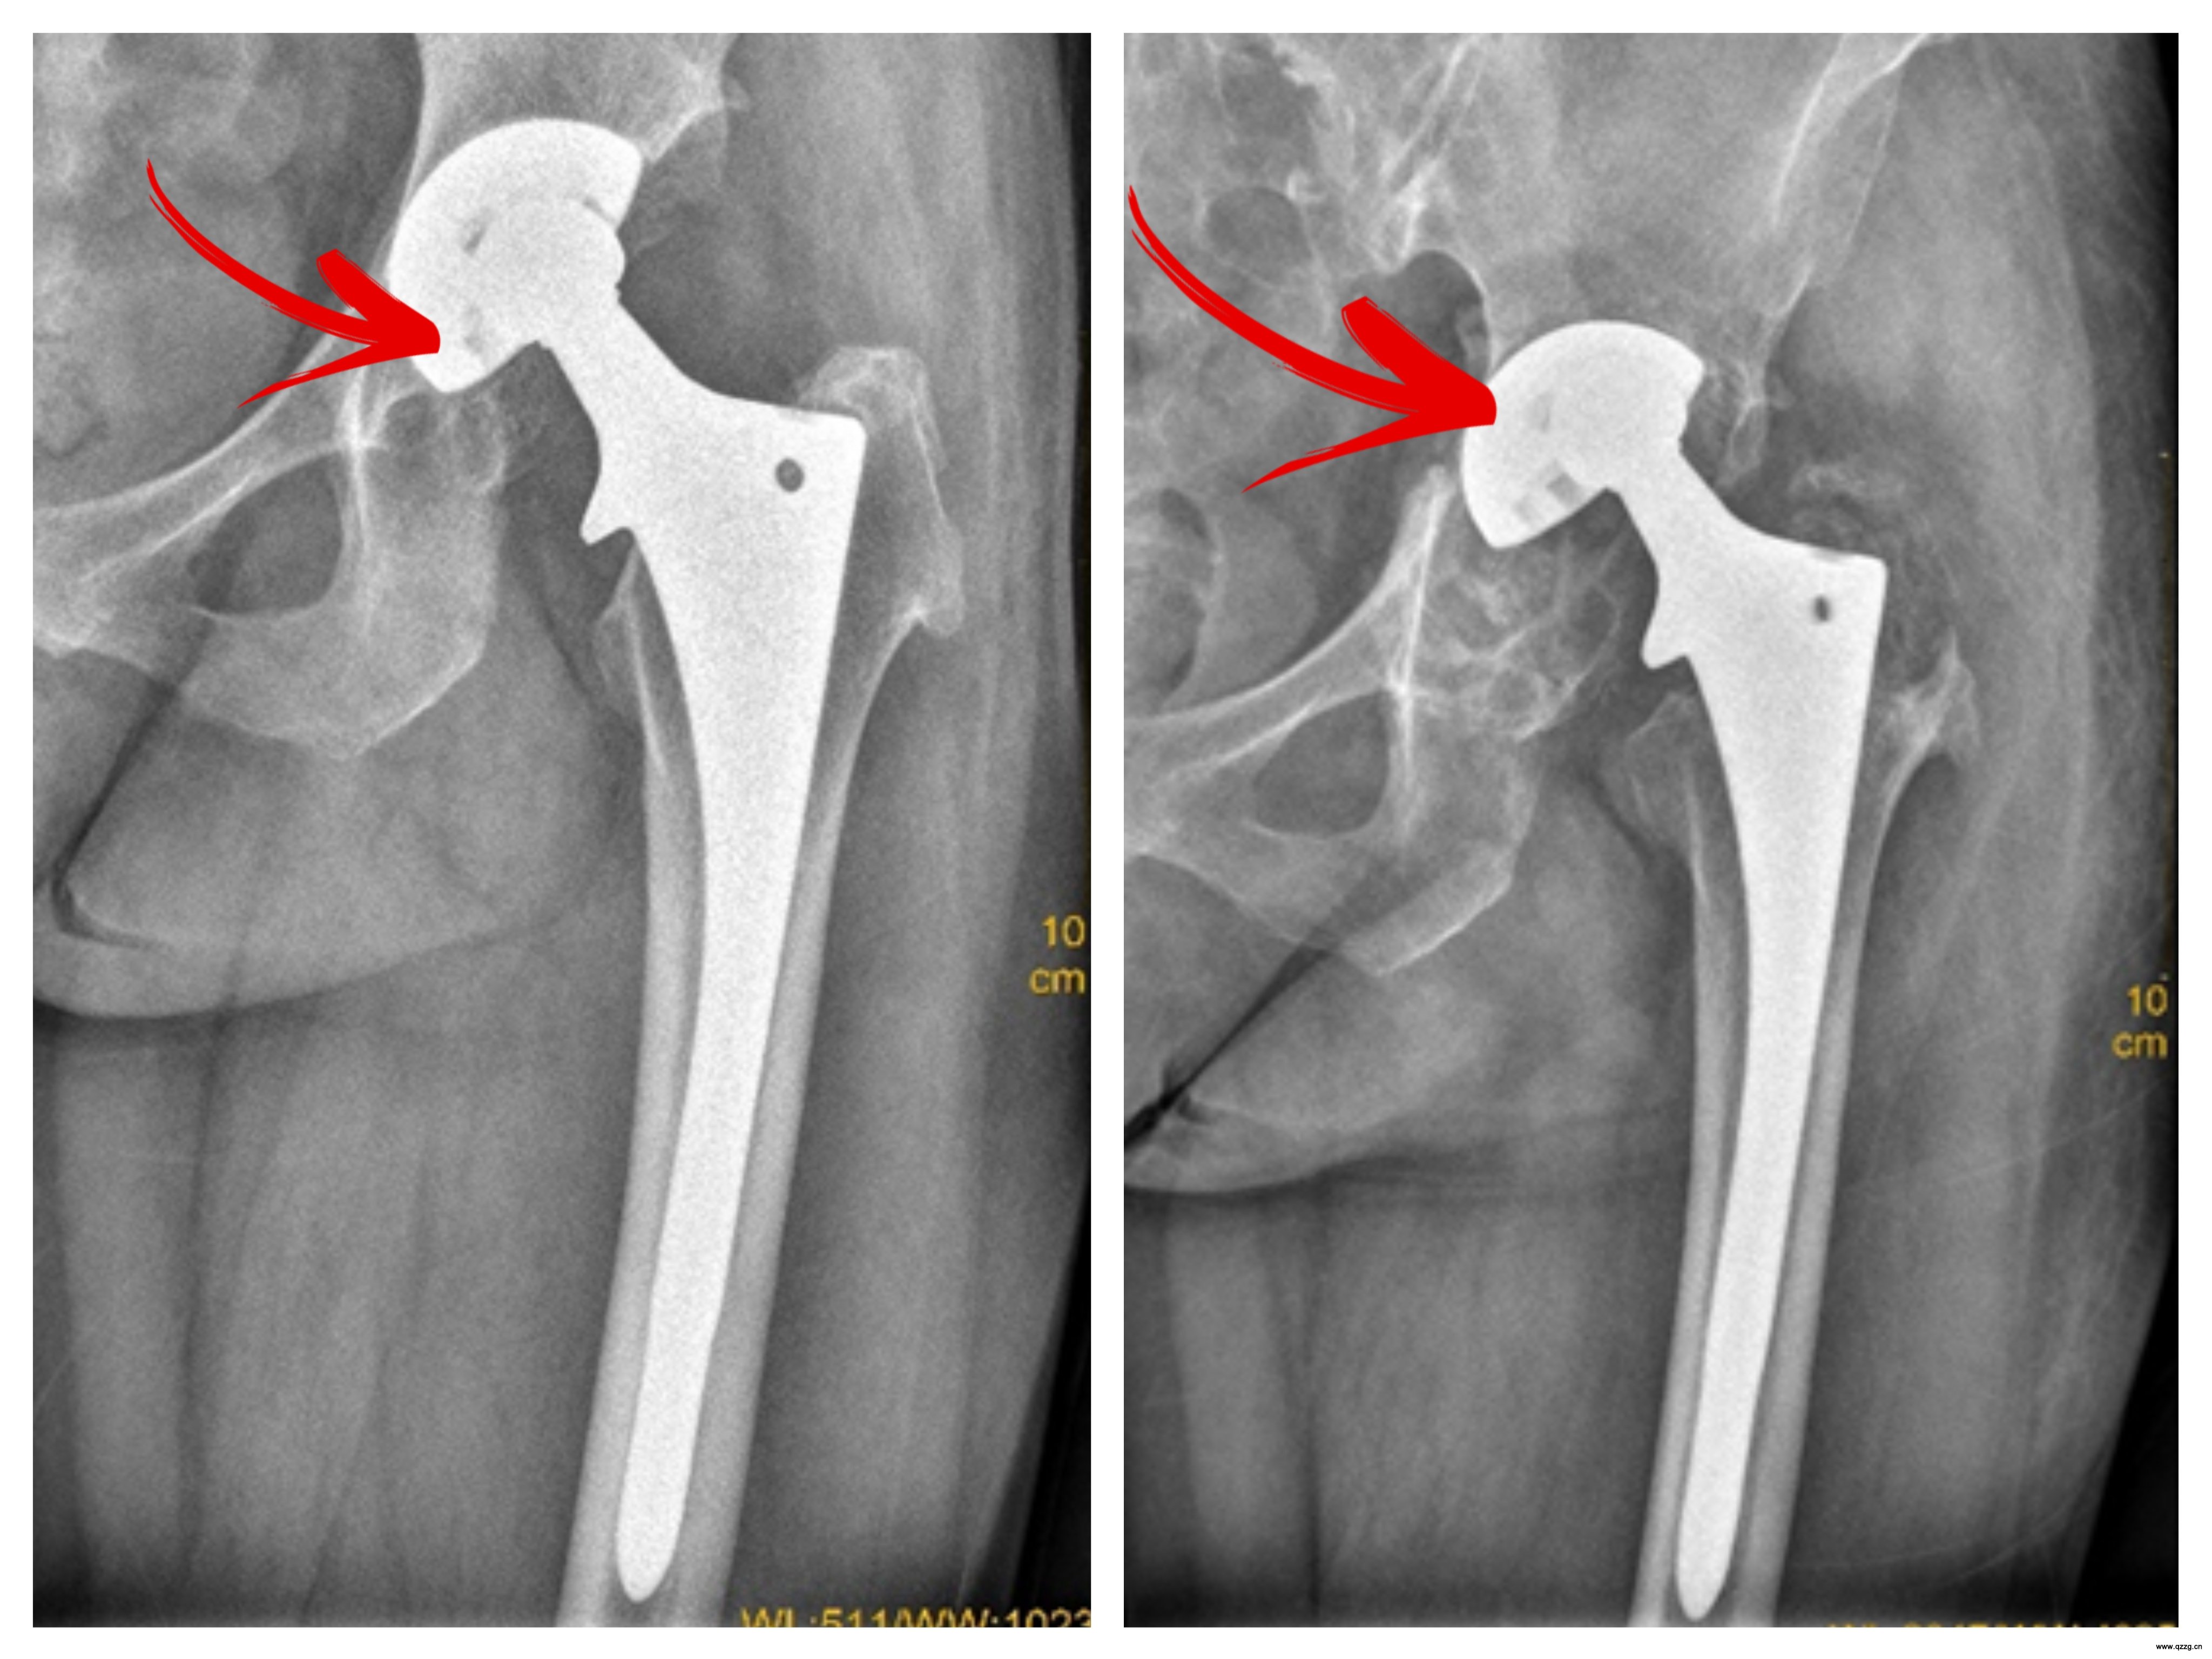

[医讯] 【正骨医讯】10年了,你很好,它还好吗?关于人工关节,请别忘记这件事 日期:2025-06-12 15:46:00 点击: 好评:0

[医讯] 【正骨医讯】10年了,你很好,它还好吗?关于人工关节,请别忘记这件事 日期:2025-06-12 15:46:00 点击: 好评:0

[医讯] 【正骨医讯】人工关节也有“保质期”!我院开设人工关节保养门诊 日期:2025-05-23 17:14:00 点击: 好评:0

[医讯] 【正骨医讯】人工关节也有“保质期”!我院开设人工关节保养门诊 日期:2025-05-23 17:14:00 点击: 好评:0